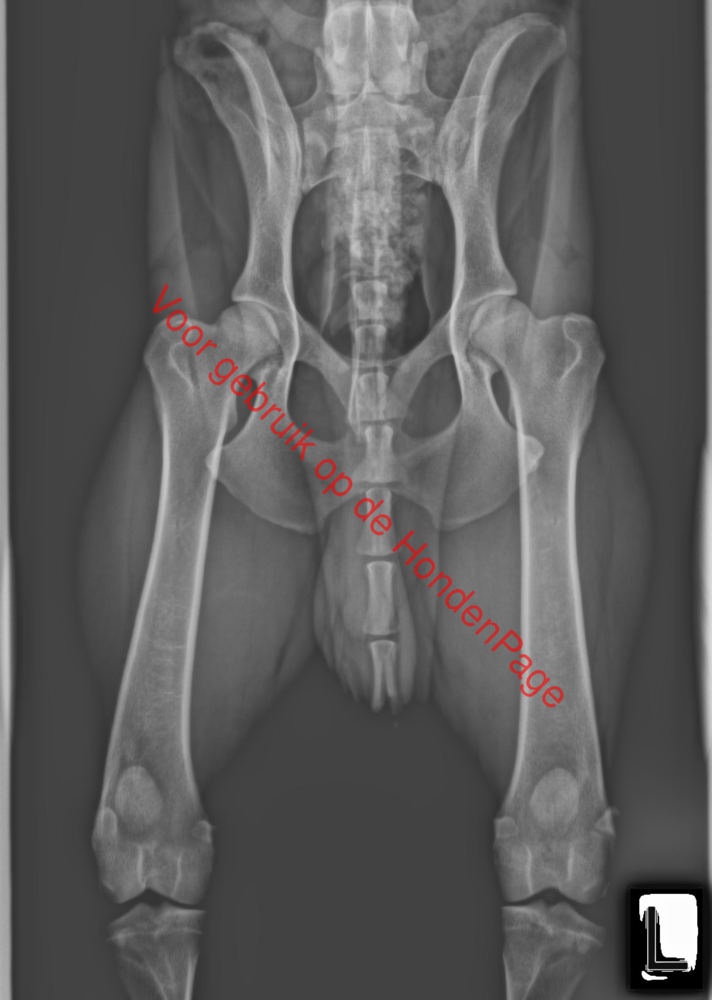

Beschrijving: Wij zijn liefhebber en fokker van de Duitse Pinscher en hebben af en toe een nestje zowel black and tan als rood. Pups worden in de woonkamer geboren en groeien daar ook op. Wij proberen gezonde, maar vooral ook lieve puppy's te fokken. Dit alles gebeurd volgens de regels van de rasvereniging en de raad van beheer. In huis hebben wij 3 honden 1 reu (Hugo) en 2 teven (Jay-Dee en Mandy), in de kleur black and tan, beide zijn ze getest op erfelijke afwijkingen en hebben ze zelfde uitslagen HD - A, Oogafwijking - vrij, Von Willembrand - N/N, Dilute - DD. De reuen die wij gebruiken zullen ook getest zijn op dezelfde erfelijke afwijkingen (HD, Oogafwijking, von Willenbrand en Dilute). Wil je weten hoe leuk Duitse Pinschers zijn? Wij hebben alle informatie voor je op een rij gezet. Wil je meer informatie kun je ons altijd bellen. Je bent ook altijd welkom voor een kopje koffie en om het ras beter te leren kennen. Onze reu is dekreu als u meer info over hem wil is dat altijd mogelijk.

Beide honden zijn getest op: HD - A, Oogafwijking - vrij, Von Willembrand - N/N, Dilute - DD.